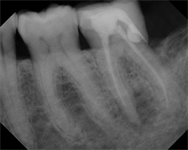

Sometimes we are quick to assume a tooth is fractured when we see lateral bone loss.  But that radiographic finding alone isn't enough to make that determination.  If you cannot visualize a fractured, and the tooth is diagnosed as a necrotic pulp, it doesn't matter how big the lucency is, it can...  Read More

Root canal failure, as well as failure of any dental treatment, is often associated with bacteria. Bacteria that is incompletely removed from the canal system during endodontic treatment will cause root canal failure. Unfortunately, sometimes that failure is not identified until months or...  Read More

As we all know, posterior teeth often get craze lines (surface cracks) in the enamel due to truama, large restorations, heavy occlusion or parafunctional habits. When these craze lines go past the enamel and into the dentin, we refer to them as cracks. Coronal cracks are very common in adult...  Read More